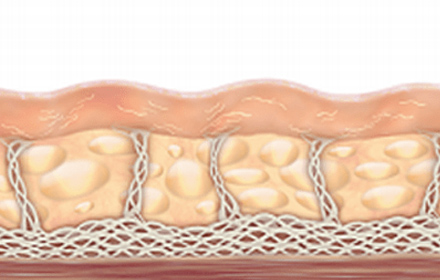

시간이 지남에 따라 피부 조직에 대한

변화는 주름과 피부 처짐을 야기합니다.

초음파 에너지를 SMAS층까지 집속시켜

전달하여 콜라겐 재생을 촉진시킵니다.

피부 표면에 손상없이 SMAS층을 응고, 수축시켜

콜라겐 재생 및 처짐이 개선됩니다.